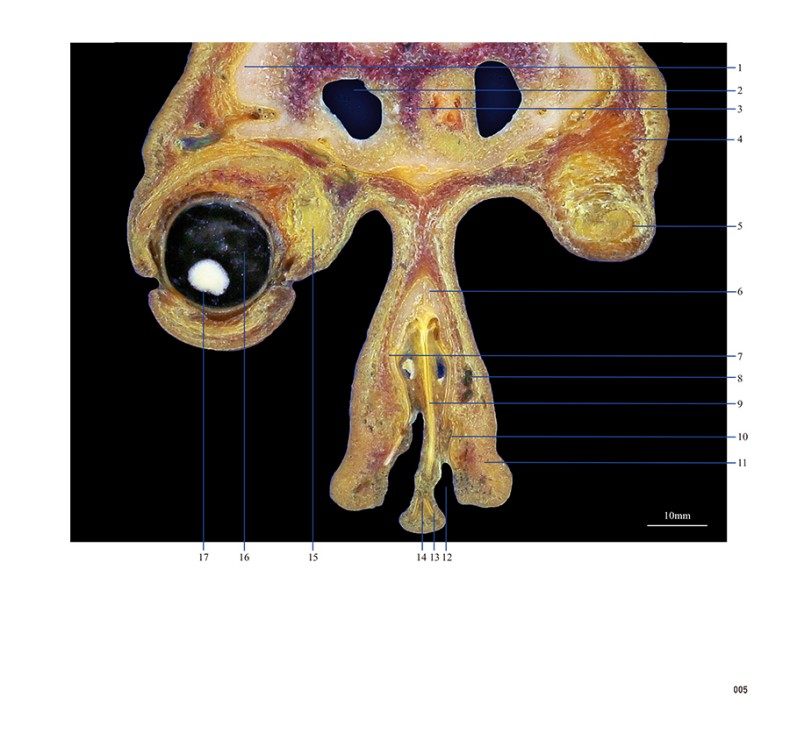

本书从数据集每隔1.2mm选取一幅图像,截取眼、耳、鼻及毗邻颅底的局部区域图像,共112幅图像。同时配以相应部位的CT图像对照。本书特色是断层解剖图利用数字图像处理技术优势,放大并清晰展示眼、耳、鼻及毗邻颅底断面的局部区域结构,组织色泽真实,甚至能够清晰显示肌肉纹理、筋膜纹路等细节结构,图像质量高于美国《人体断层解剖学彩色图谱》(引进版)类似图谱图像质量。对眼科、耳鼻咽喉科医生理解相关解剖结构有较大帮助。